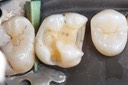

Photos of Clinical Operations

Mentors: Drs. Randy Allan, Greg Card, Peter Kearney

Clubs #44 and #50 joint meeting